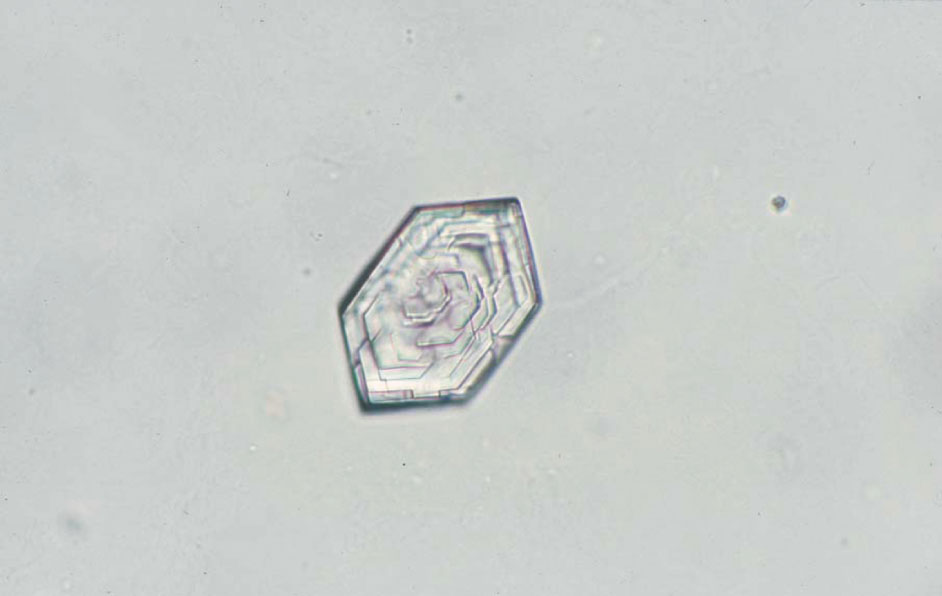

シスチン結晶 40× 無染色

Cystine crystals 40× No staining

無色で六角形の板状結晶である。いく層も重なり合うとコレステロール結晶に類似する場合がある。酸性尿でみられる。細菌尿では直ちに溶解し観察が困難な場合がある。pH 6.0

A colorless, hexagonal plate-shaped crystal. When the crystals overlap in many layers, they may look similar to cholesterol crystals. Cystine crystals are found in acidic urine. In bacterial urine, they may dissolve instantly, making them difficult to observe. pH 6.0